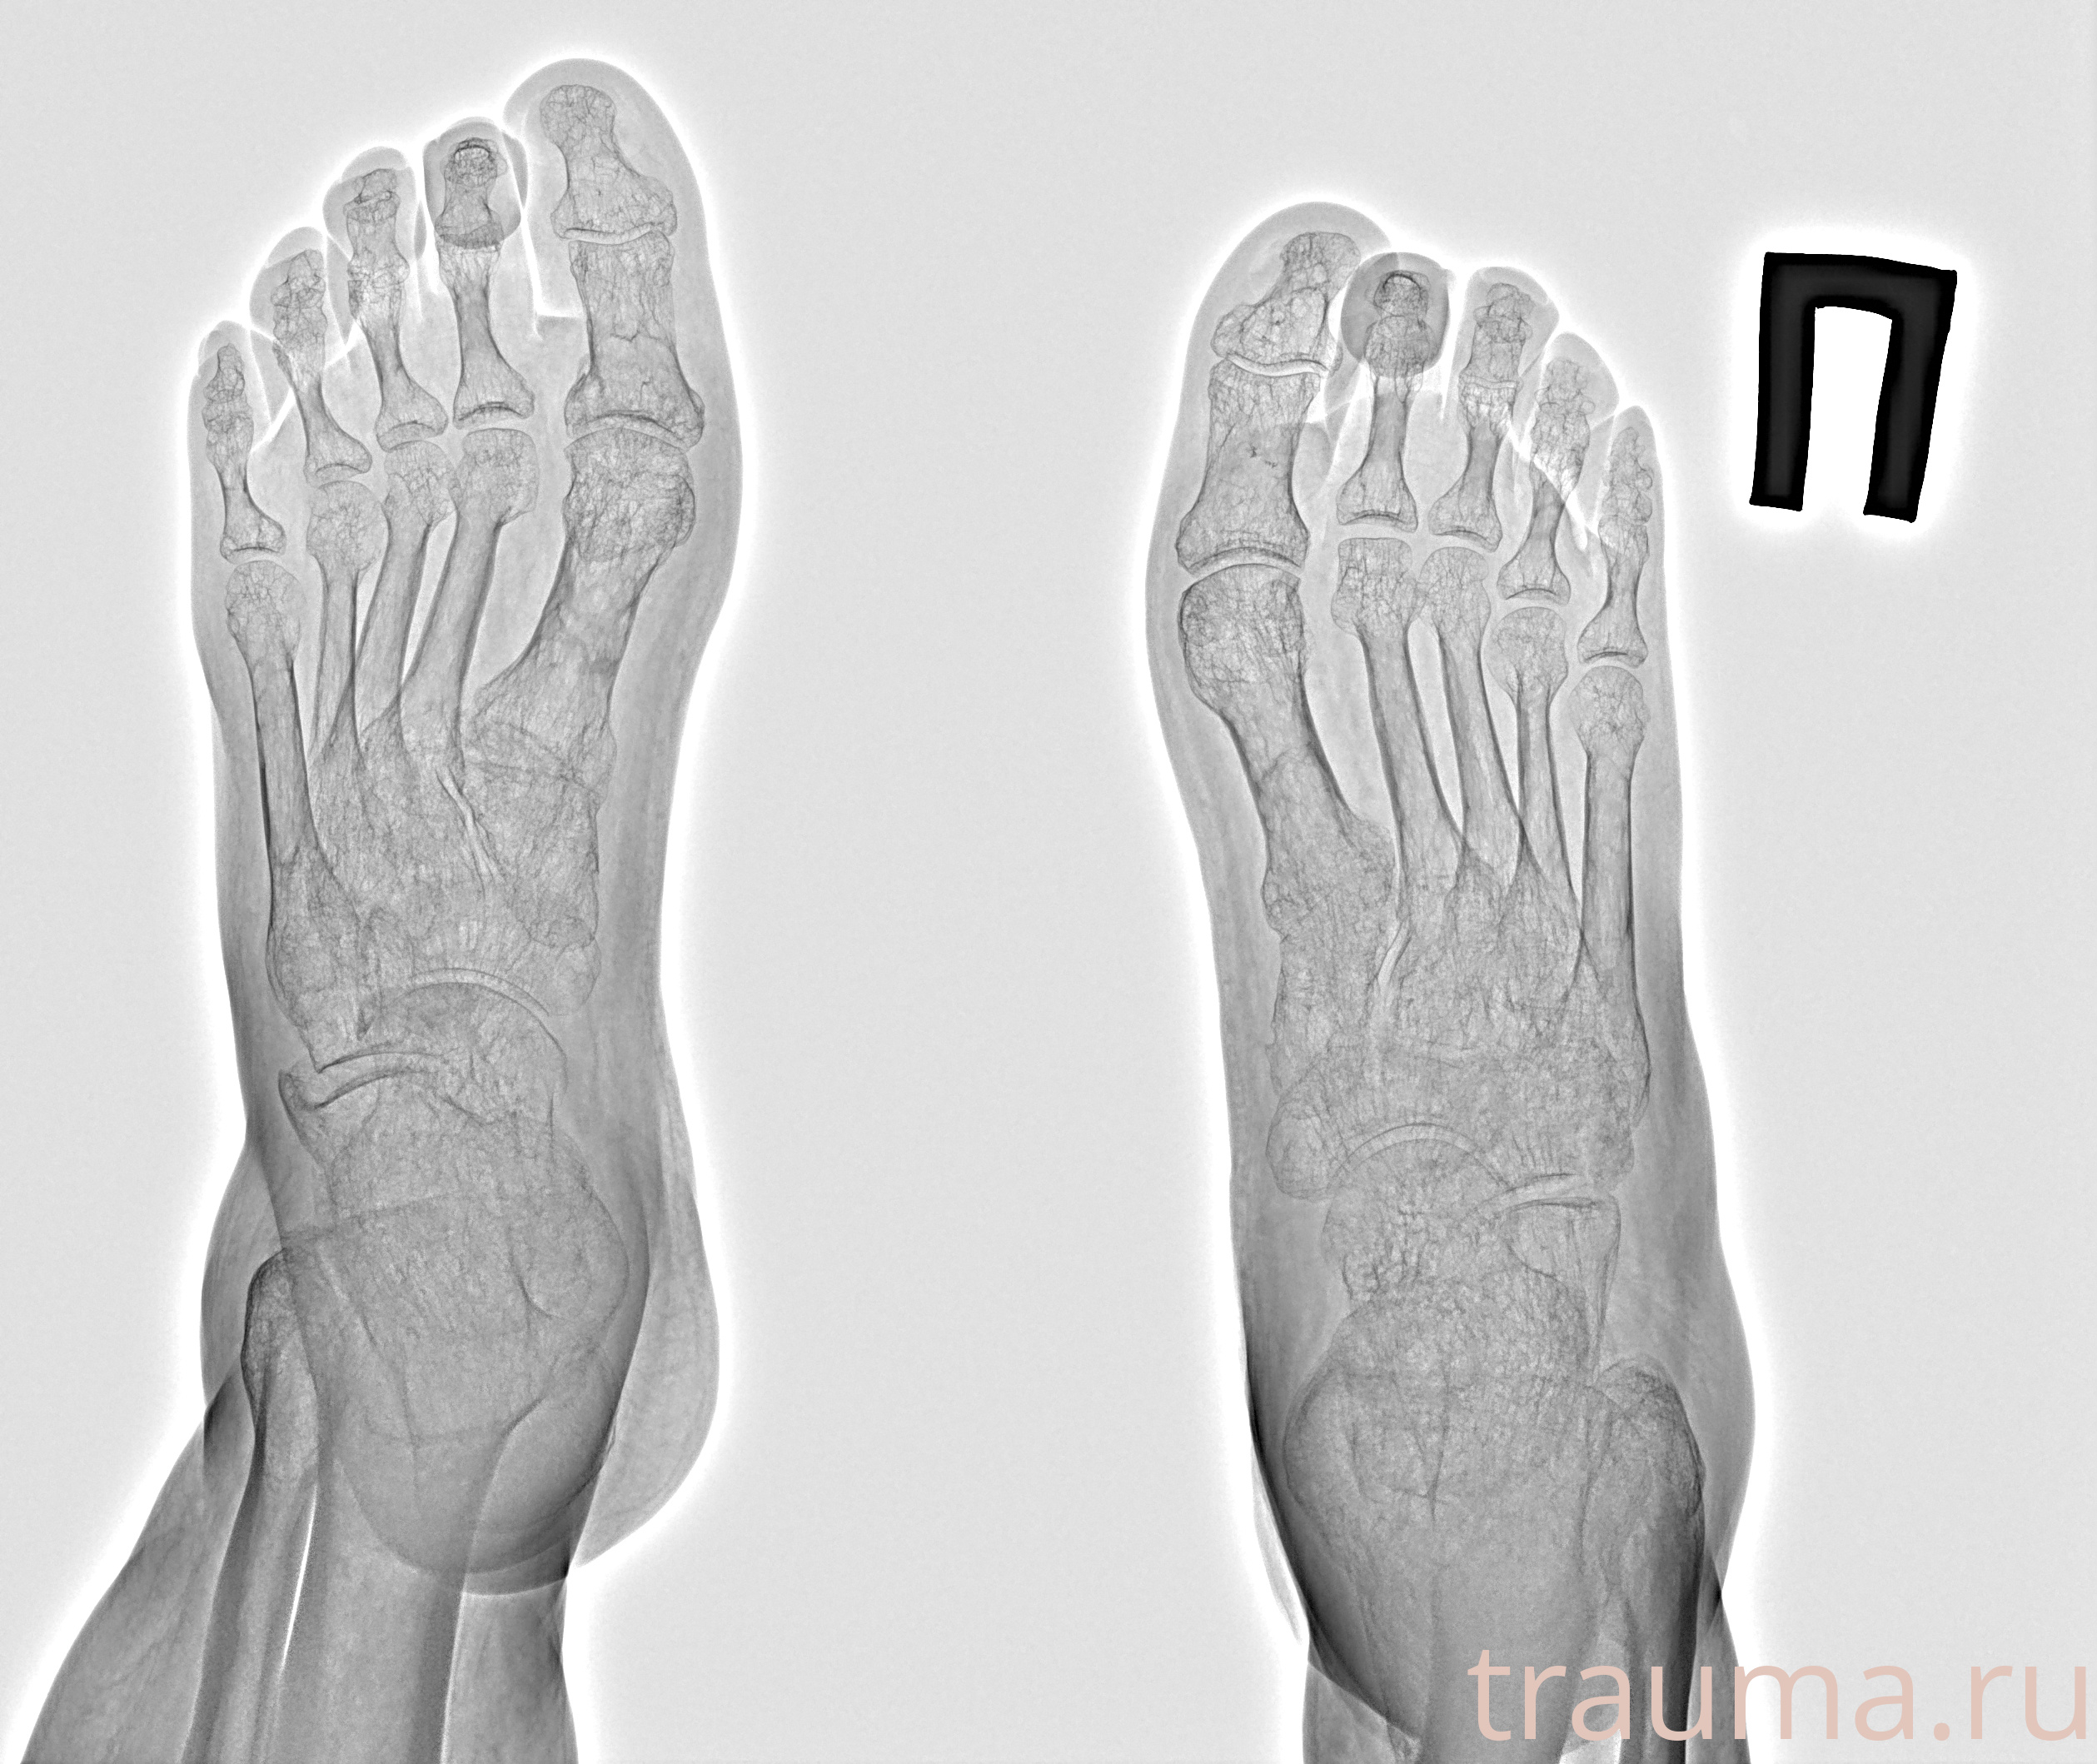

Рентген на дому: по вашему адресу приезжает врач-рентгенолог, травматолог-ортопед с мобильным рентгеновским аппаратом, проводит диагностику травмы или заболевания, делает необходимые рентгенограммы, дает рекомендации по дальнейшему лечению. Получить качественные снимки в домашних условиях возможно благодаря уникальной методике, разработанной МосРентген Центром для института  Склифосовского